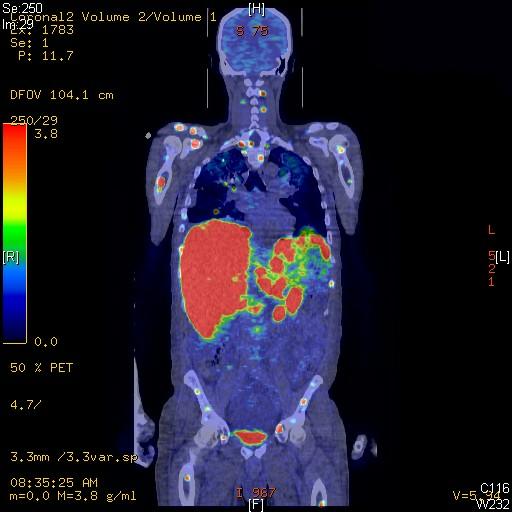

Facilitate learning with our scientific Pet/ct Lymphatic System gallery of hundreds of educational images. accurately representing photography, images, and pictures. perfect for research publications and studies. Browse our premium Pet/ct Lymphatic System gallery featuring professionally curated photographs. Suitable for various applications including web design, social media, personal projects, and digital content creation All Pet/ct Lymphatic System images are available in high resolution with professional-grade quality, optimized for both digital and print applications, and include comprehensive metadata for easy organization and usage. Explore the versatility of our Pet/ct Lymphatic System collection for various creative and professional projects. Multiple resolution options ensure optimal performance across different platforms and applications. Whether for commercial projects or personal use, our Pet/ct Lymphatic System collection delivers consistent excellence. Professional licensing options accommodate both commercial and educational usage requirements. Each image in our Pet/ct Lymphatic System gallery undergoes rigorous quality assessment before inclusion. Time-saving browsing features help users locate ideal Pet/ct Lymphatic System images quickly. Advanced search capabilities make finding the perfect Pet/ct Lymphatic System image effortless and efficient. Comprehensive tagging systems facilitate quick discovery of relevant Pet/ct Lymphatic System content. Instant download capabilities enable immediate access to chosen Pet/ct Lymphatic System images.